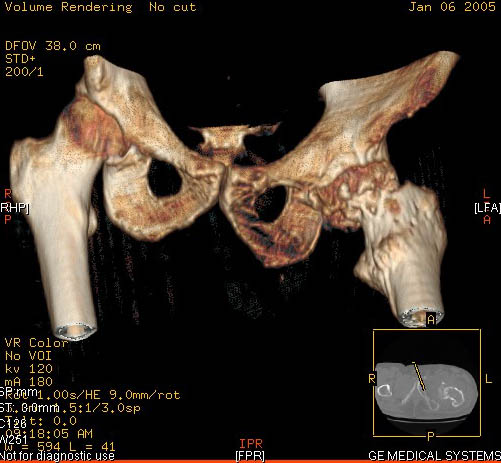

И снова вопрос по эндопротезированию: Пациенту 51 год. Болен с 2000 г, когда отметил умеренные, нараостающие боли в в/3 левого бедра, прогрессирующую контрактуру лев Т/Б сустава.

05.12.04 после падения на бедро боли резко усилились, нога стала неопорной. На рентгенограмме обнаружен патологический перелом шейки бедренной кости. Обследован в отделении костной онкологии. Результат биопсии: асептический некроз проксимального отдела бедренной кости. Вопрос: выбор технологии эндопротезирования - цементная или бесцементная версия. Заранее благодарю! С уважением,А.В.Владзимирский

Проксимальный отдел бедра не виден достаточно на представленных рентгенограммах; но то, что видно, как раз наводит на мысли о цементной фиксации - цилиндрический канал, измененный calcar, кистозные изменения в области большого вертела и т.д.

Evgueny Tchekashkine 01 Февраль 2005, 04:15

Как то очень подозрительно выглядит проксимальный отдел бедра для такого очень простого гистологического заключения. Вы уверены, что гистология настолько благополучна и в каком варианте она выполнялась: пункционная или открытая с забором костного блока? Не уверен на все сто , но область проксимального отдела бедра - одно из излюбленных мест для гигантоклеточной опухоли, которая зачастую озлакочествляется (имел два подобных наблюдения). Из своей практики могу сказать, что, к сожалению, информативность пункционной биопсии не сравнима с открытой техникой. Поэтому прежде чем решать цементный или бесцементный протез использовать, я бы повторил биопсию в сочетании со сканированием скелета, сывороточная щелочная фосфатаза, кальций, фосфор сыворотки, СОЭ, С- реактивный белок,

Вполне вероятно, что разговор может пойти об опухолевом протезе или Вагнере...

Soglasen s Евгений И Чекашкин, proximal Femur does not look right. Sarcoma? Pagets, Osteomyelitis?. Technicality of the implantaion will be dependent upon underlying pathology, and the surgeon's level of comfort.

Действительно, проксимальный отдел бедра выглядит подозрительно. По-моему напоминает болезнь Педжета. Кстати, гистологическое заключение в таком случае часто звучит как "хроническое воспаление", "асептический некроз с элементами лейкоцитарной инфильтрации" и т.п. Далеко не все патоморфологи имеют достаточный опыт для дифференцировки костной патологии.

Однако, вне зависимости от диагноза, проблема "с цементом или без" остается. Онко-эндопротезы (так же как и ревизионные) тоже могут быть бесцементной фиксации. И в нешей клинике есть положительный опыт их применения. Поразительно, насколько полярными могут быть мнения в этом вопросе, причем аргументация ссылками на литературу практически лишена смысла - достаточно много статей с равной степенью уверенности пропогандирующих и то и другое. Ссылки на собственный опыт тоже имеются разные. Лично я больше склоняюсь к бесцементной технике. Однако советую запастись и цементными компонентами и окончательно решить, что применять во время операции.